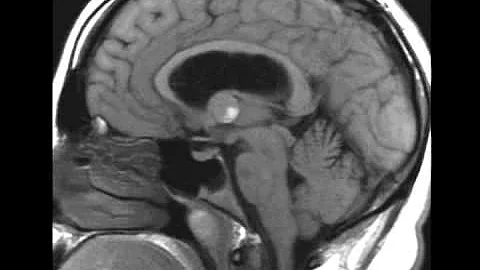

Hydrocephalus Due To Colloid Cyst Animation By Cal Shipley, M.d.

Hydrocephalus, Brainstem Herniation and Stroke due to obstruction of the Foramen of Monro by a Colloid Cyst NEU083 Related ...